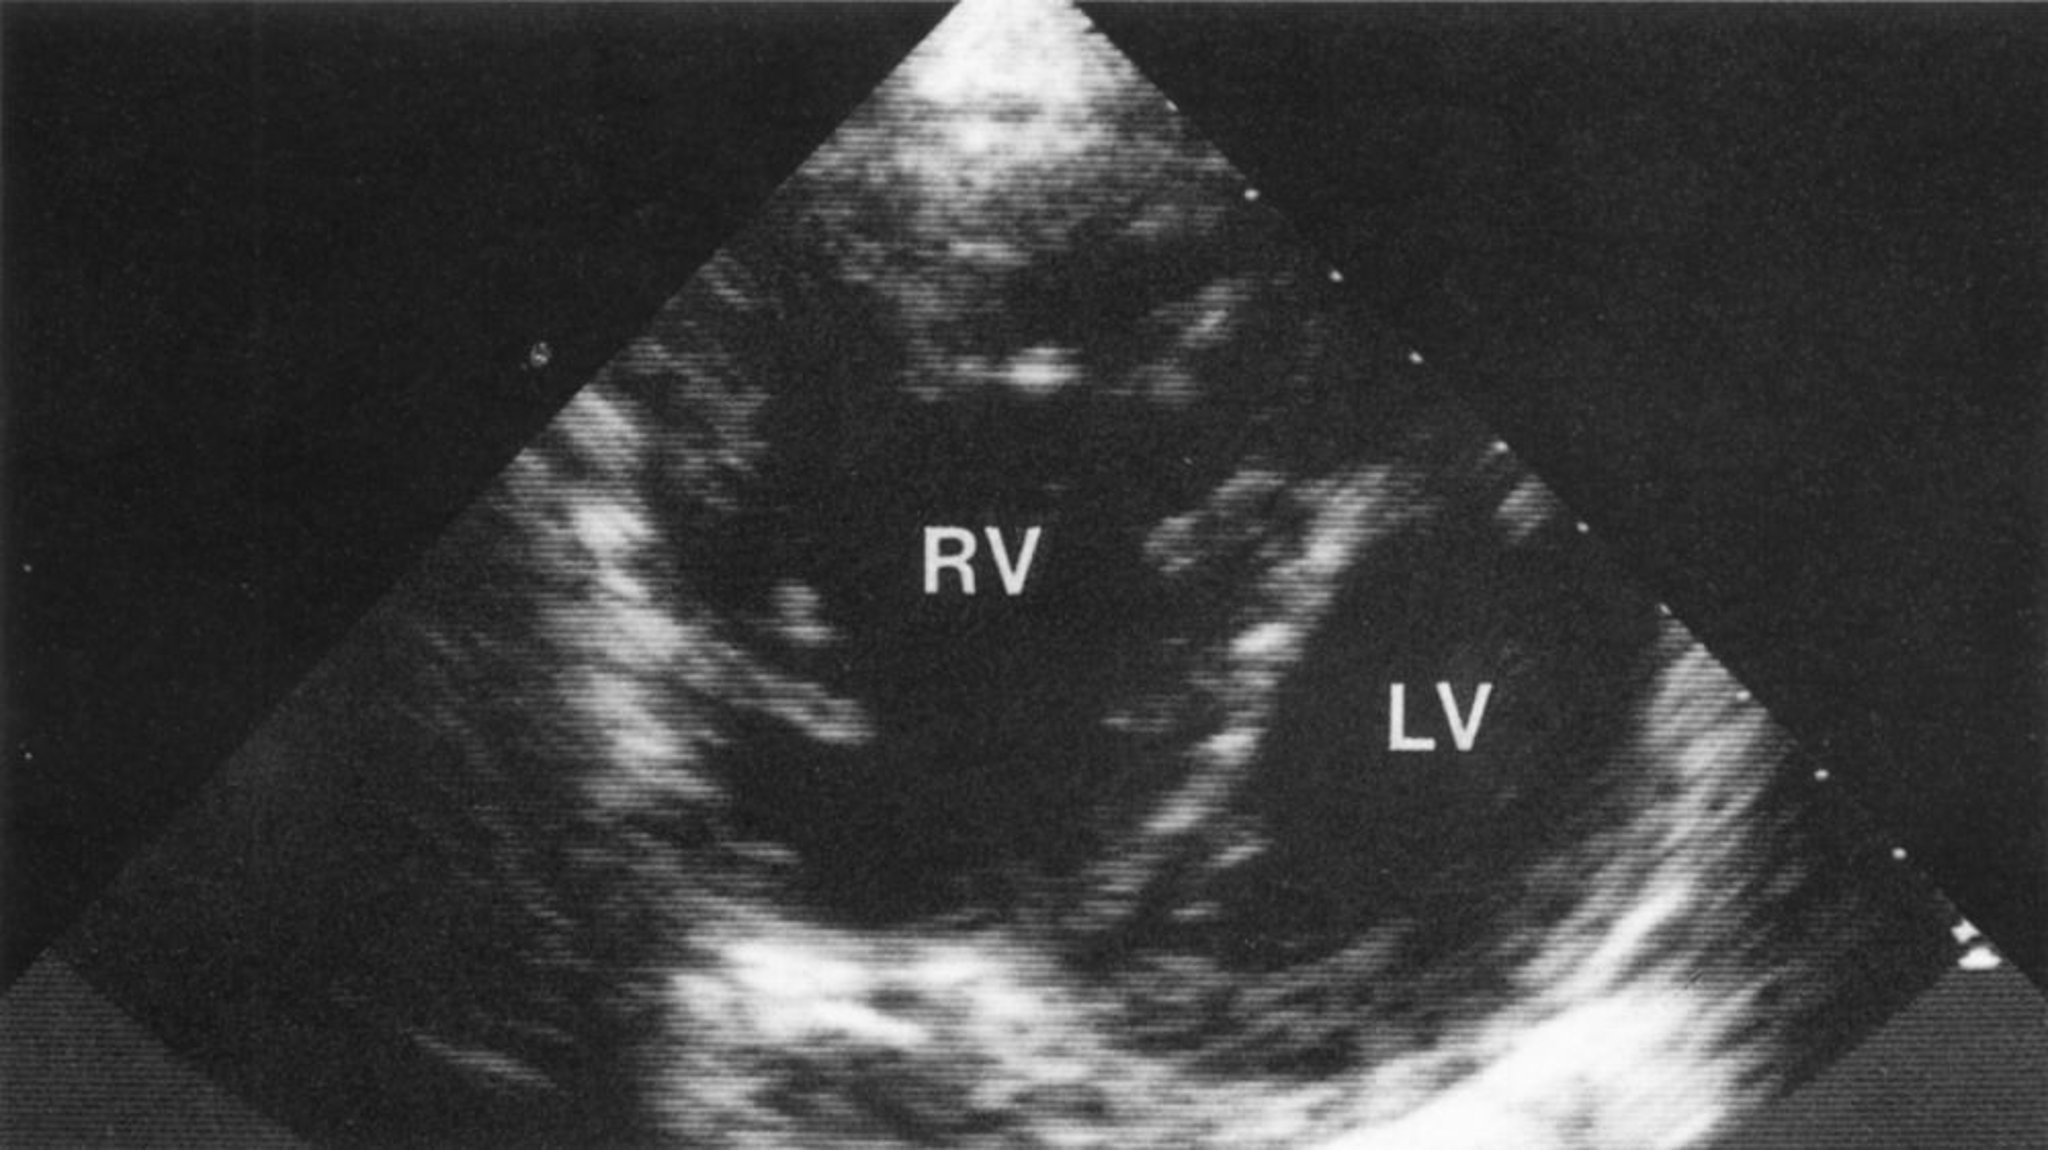

Die Echokardiographie oder Szintigraphie wird zur Bestimmung der LV- und RV-Funktion durchgeführt, die Echokardiographie kann den systolischen RV-Druck bestimmen, wird aber häufig in der technischen Anwendung durch die Lungenkrankheit limitiert. Eine kardiale MRT kann bei einigen Patienten hilfreich sein, um die kardiale Kammern und Funktion zu bewerten. Eine Rechtsherzkatheruntersuchung kann zur Bestätigung der Befunde erforderlich sein.